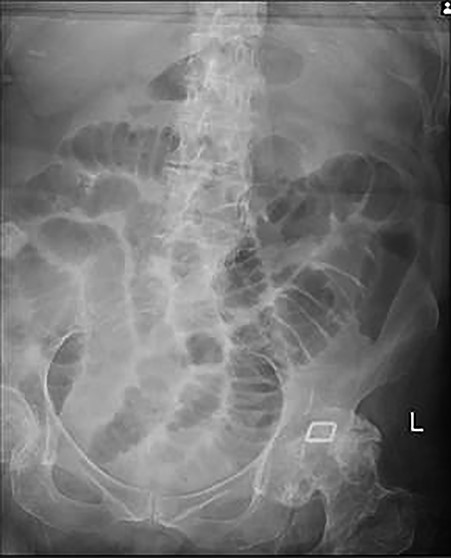

Plain abdominal X-ray demonstrated a calcified lesion on the right as well as distended loops of small bowel (Fig. 1). Abdomino-pelvic contrast CT scan showed an abnormal gallbladder containing pockets of air and a fistulation through the lateral part of D2,with a 22 mm calcified lesion within the ascending colon (Fig. 2a–d). Based on the history, physical examination and CT scan findings, our diagnosis was of resolving gallstone ileus.

Plain abdominal X-ray at presentation demonstrating gallstone as well as distended loops of small bowel.